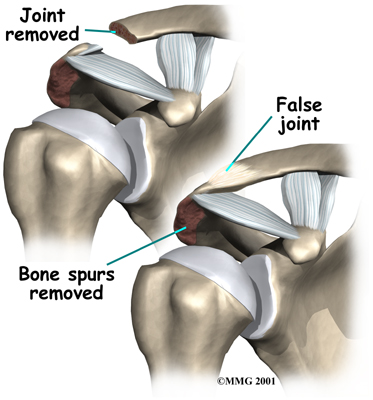

The most common procedure for AC joint osteoarthritis is resection arthroplasty. A resection arthroplasty involves removing a small portion of the end of the clavicle. This leaves a space between the acromion (the piece of the scapula that meets your shoulder) and the cut end of the clavicle, where the joint used to be. Your surgeon will take care not to remove too much of the end of the clavicle to prevent any damage to the ligaments holding the joint together. Usually only a small portion is removed, less than one cm (about three-eighths of an inch). As your body heals, the joint is replaced by scar tissue. Remember, the AC joint doesn't move much, but it does need to be flexible. The scar tissue allows movement but stops the bone ends from rubbing together.

This procedure can be done in two ways. Today, it is more common to do this procedure using the arthroscope. An arthroscope is a slender tool with a tiny TV camera on the end. It lets the surgeon work in the joint through a very small incision. This may result in less damage to the normal tissues surrounding the joint, leading to faster healing and recovery.